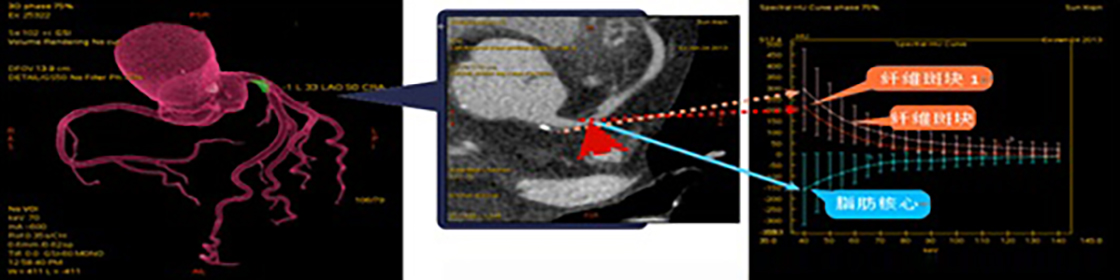

由于軟斑塊的危害程度在一定程度上高于鈣化斑塊,如CT檢查能增加了解軟斑塊的性質(zhì),對于斑塊的穩(wěn)定性判斷及治療將有極大幫助。另外動態(tài)觀察軟斑塊性質(zhì)變化可為病變愈后趨勢判斷提供一定的依據(jù)。實現(xiàn)此功能要求CT檢查在傳統(tǒng)的形態(tài)學(xué)成像基礎(chǔ)上增加組織或病變成份判斷的功能。因此對臨床醫(yī)學(xué)更有助益的應(yīng)為心臟冠脈能譜成像,應(yīng)用能譜掃描技術(shù)可以對冠脈斑塊成份性質(zhì)進(jìn)行分析(圖4),預(yù)判斑塊的危險性或斑塊演變進(jìn)程,為進(jìn)一步治療提供信息。文獻(xiàn)介紹及目前國內(nèi)一些醫(yī)院實際使用效果顯示能譜CT技術(shù)的發(fā)展已可以在自然心率下(無需控制心率)對心臟及冠脈進(jìn)行常規(guī)成像和能譜成像,成為臨床應(yīng)用覆蓋最廣的超高端CT。